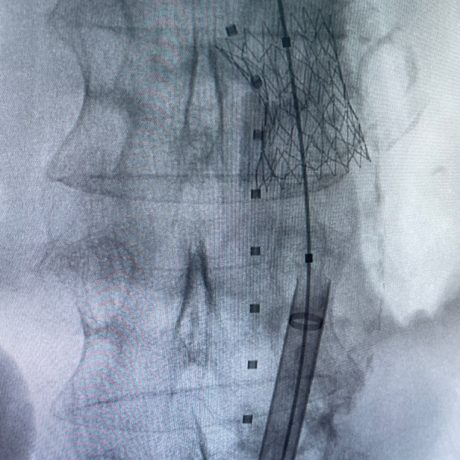

Soluciones vasculares

Portfolio técnico en intervencionismo endovascular. Implantables y consumibles para cada procedimiento.